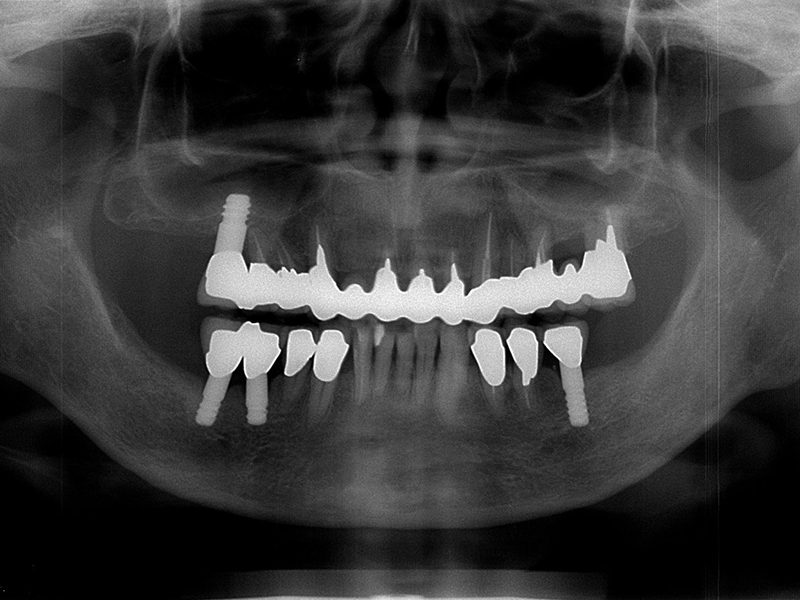

治療後のパントモ写真